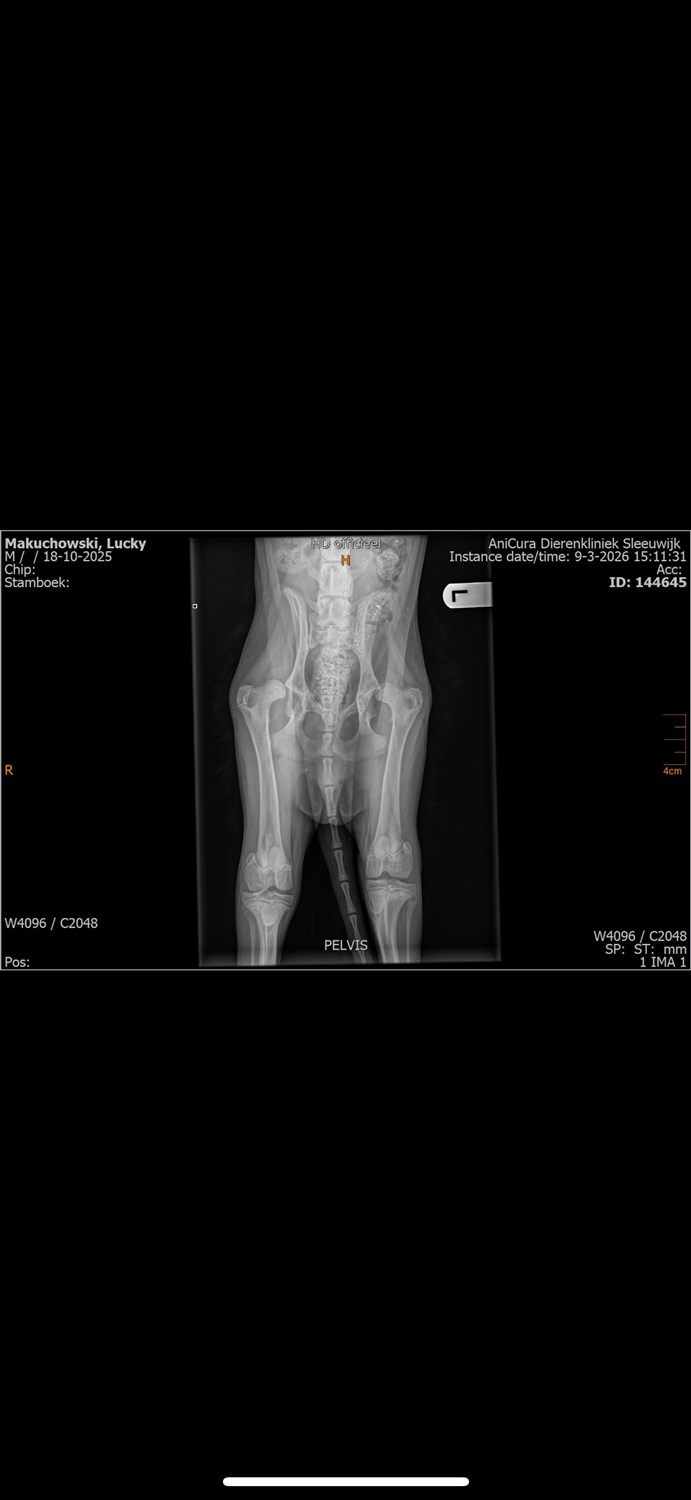

Ik heb lang getwijfeld of ik hulp moest vragen. Het is niet makkelijk, maar ik weet dat we hiermee ons kleine vriendje kunnen redden. We dachten er al een tijdje over na om een hond in huis te nemen. Eindelijk was het moment daar. Hij zou de beste vriend worden van onze 8-jarige zoon Tymek, die er al heel lang van droomde een hond te hebben. Toen Lucky bij ons aankwam, was hij een blije, lachende pup met een prachtige vacht. Hij speelde graag met kinderen en er was geen enkel teken dat er iets mis was. Helaas veranderde alles op een dag. De vier maanden oude Lucky verloor plotseling de kracht om te staan. Hij begon ongemakkelijk te zitten en had moeite met bewegen. Zonder aarzelen gingen we naar de dierenarts. De diagnose was een enorme klap voor ons: Lucky heeft ernstige bilaterale heupdysplasie. We wonen in Nederland en de dierenarts vertelde ons ronduit: de enige oplossing was een zeer dure operatie of... euthanasie, omdat de ziekte immense pijn veroorzaakt. Ik verliet het kantoor met tranen in mijn ogen, ik kon niet geloven dat dit zijn toekomst zou zijn. Na thuiskomst ben ik overal hulp gaan zoeken. Ik heb scans naar artsen in Polen en andere landen gestuurd. Het bleek dat Lucky met dit probleem geboren was, maar dat er een kans voor hem was. De enige manier om hem van de pijn te verlossen en hem een normaal leven te laten leiden, is een operatie – een totale heupprothese (THR) of een volledige heupprothese (FHO). De kosten van de behandeling bedragen ongeveer € 3.000, plus een lange en kostbare revalidatie. Lucky moet eerst revalideren, vooral op een loopband om zijn spieren te versterken. Na de operaties staat hem nog een lang herstelproces te wachten. We willen er alles aan doen om ervoor te zorgen dat hij kan rennen, met onze zoon kan spelen en pijnvrij kan leven. Daarom vragen we om hulp. Elke donatie, hoe klein ook, brengt ons dichter bij Lucky's kans op een normaal leven. Ik geloof in de kracht van mensen en dat we hem samen kunnen helpen. We danken jullie van harte voor elke cent en elke keer dat jullie dit bericht delen. ❤️